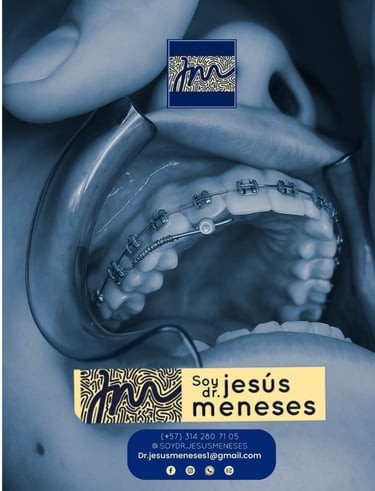

Ortodoncia

Alineamos tus dientes con tecnología avanzada para resultados naturales.

Galería

Sonrisas reales y tecnología en acción